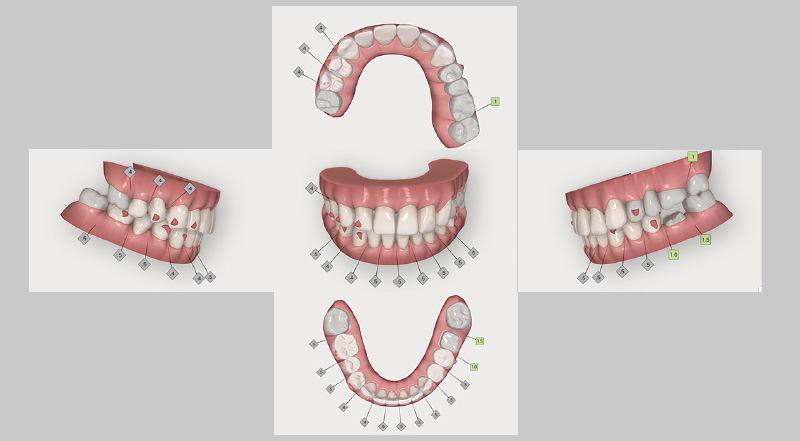

図5 インプラント埋入後に計画した、クリンチェック治療計画の矯正治療前画像。この症例では、第一大臼歯まで矯正可能な「iGo Plus」を選択。 -

図6 「iGo Plus」クリンチェック治療計画の、矯正治療後のシミュレーション画像。 -